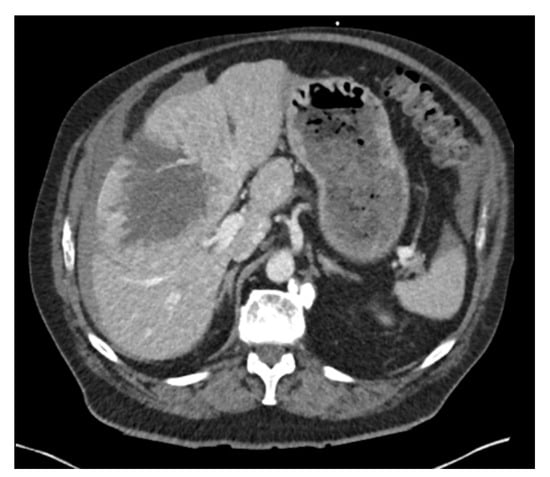

2. Case